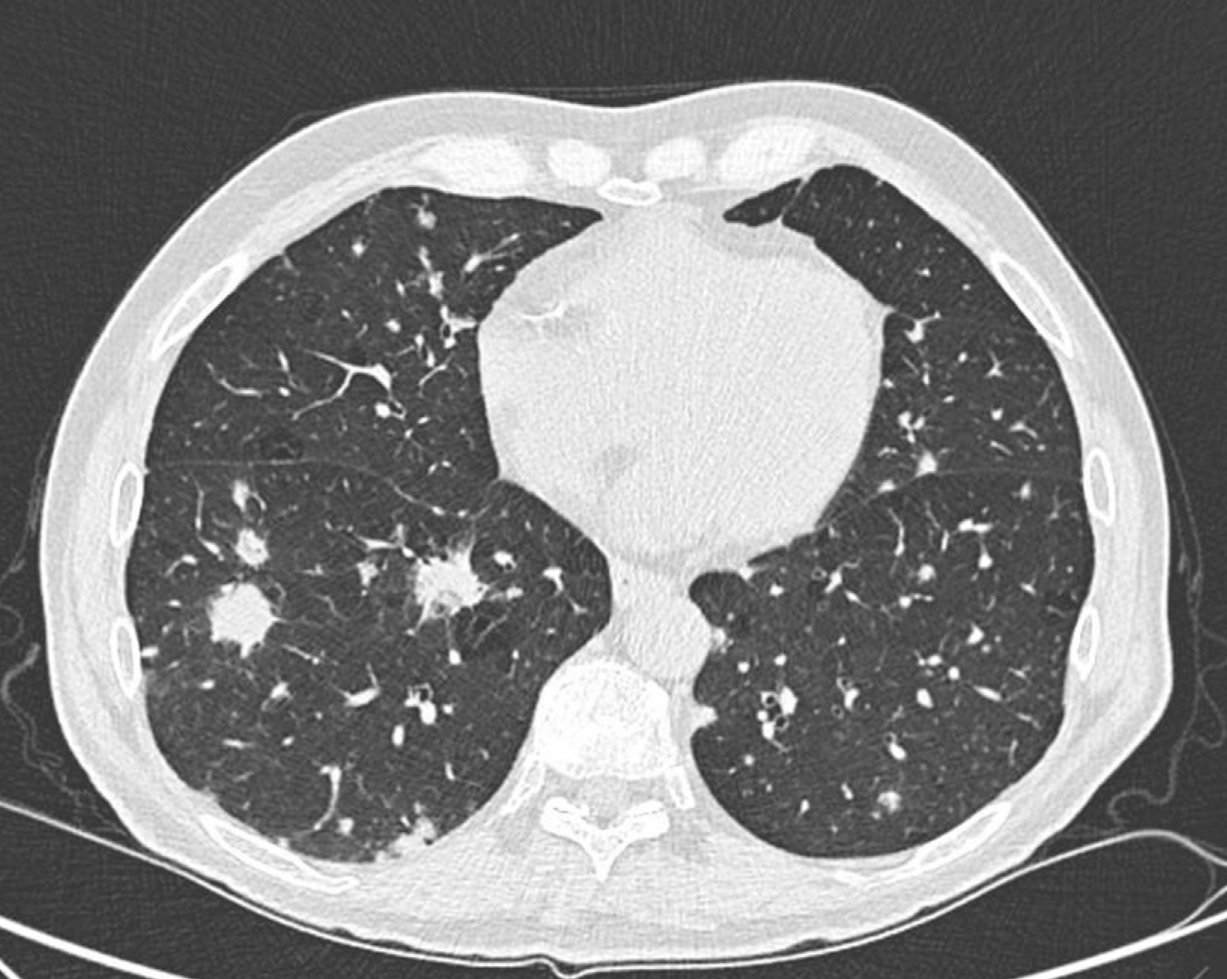

5.7.1 Imaging

CT Findings Suggestive of IPA:

- Nodules with halo sign (ground-glass surrounding dense core)

- Air-crescent sign (late finding with neutrophil recovery)

- Wedge-shaped infiltrates

- Cavitation

The halo sign (ground-glass attenuation surrounding a nodule) is relatively specific for angioinvasive mold infection in neutropenic patients, particularly in the first week of infection.

- CT findings: Centrilobular nodules, tree-in-bud pattern

| 0-3 | Hyphal tissue invasion | Macronodule ± halo sign | GM may be negative |

| 5-7 | Hemorrhage, infarction | Dense consolidation | Serum GM positive |

| 10-12 | Extensive necrosis | Hypodense sign | High fungal burden |

| 15-18 | Neutrophil recovery, cavitation | Air-crescent sign | May persist |